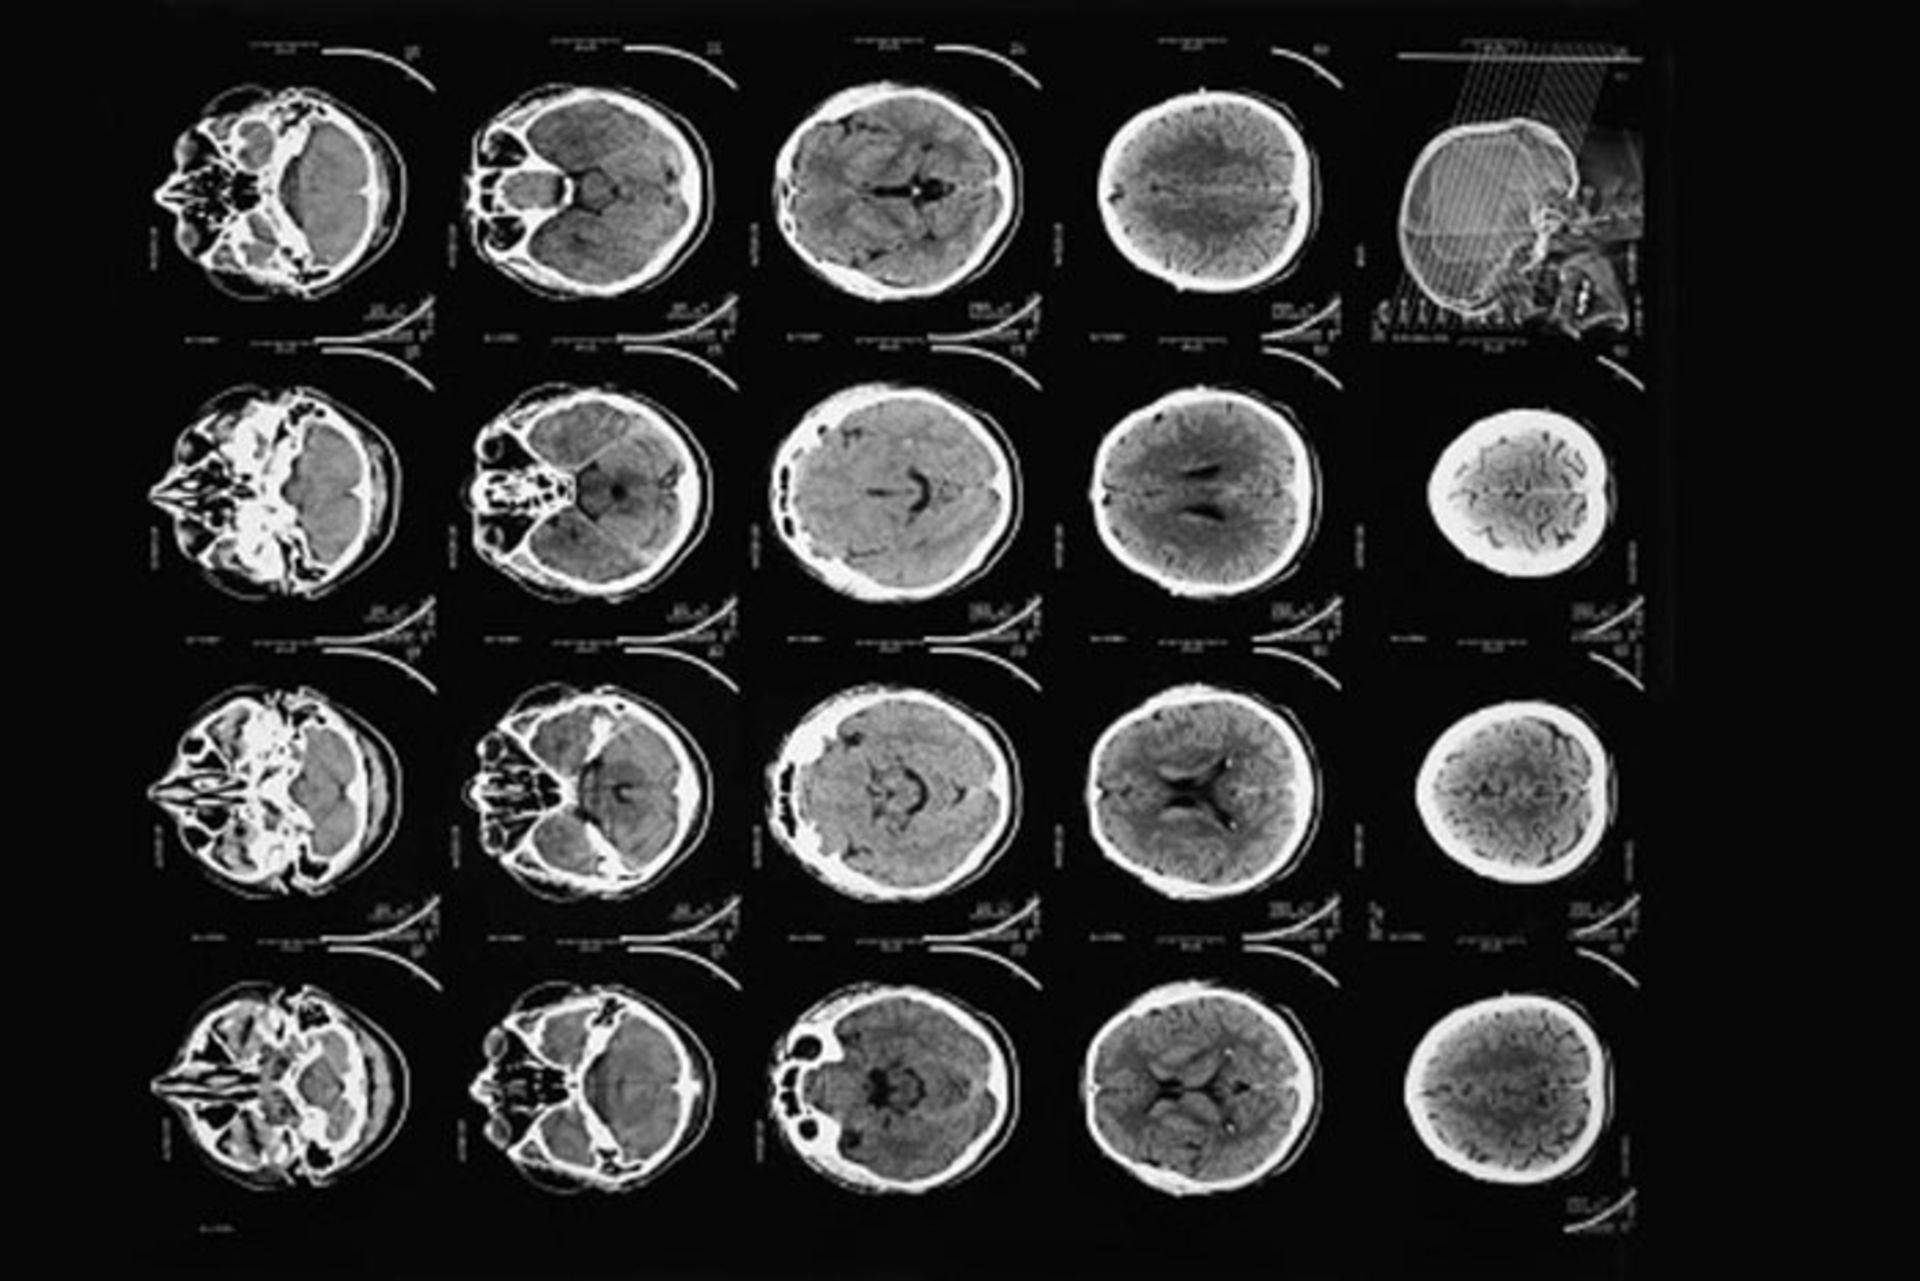

تصویر اسکن مغزی

سی‌تی‌ اسکن‌های مدرن تصاویری با وضوح بیشتر از برش‌های مغز انسان به‌دست می‌دهند